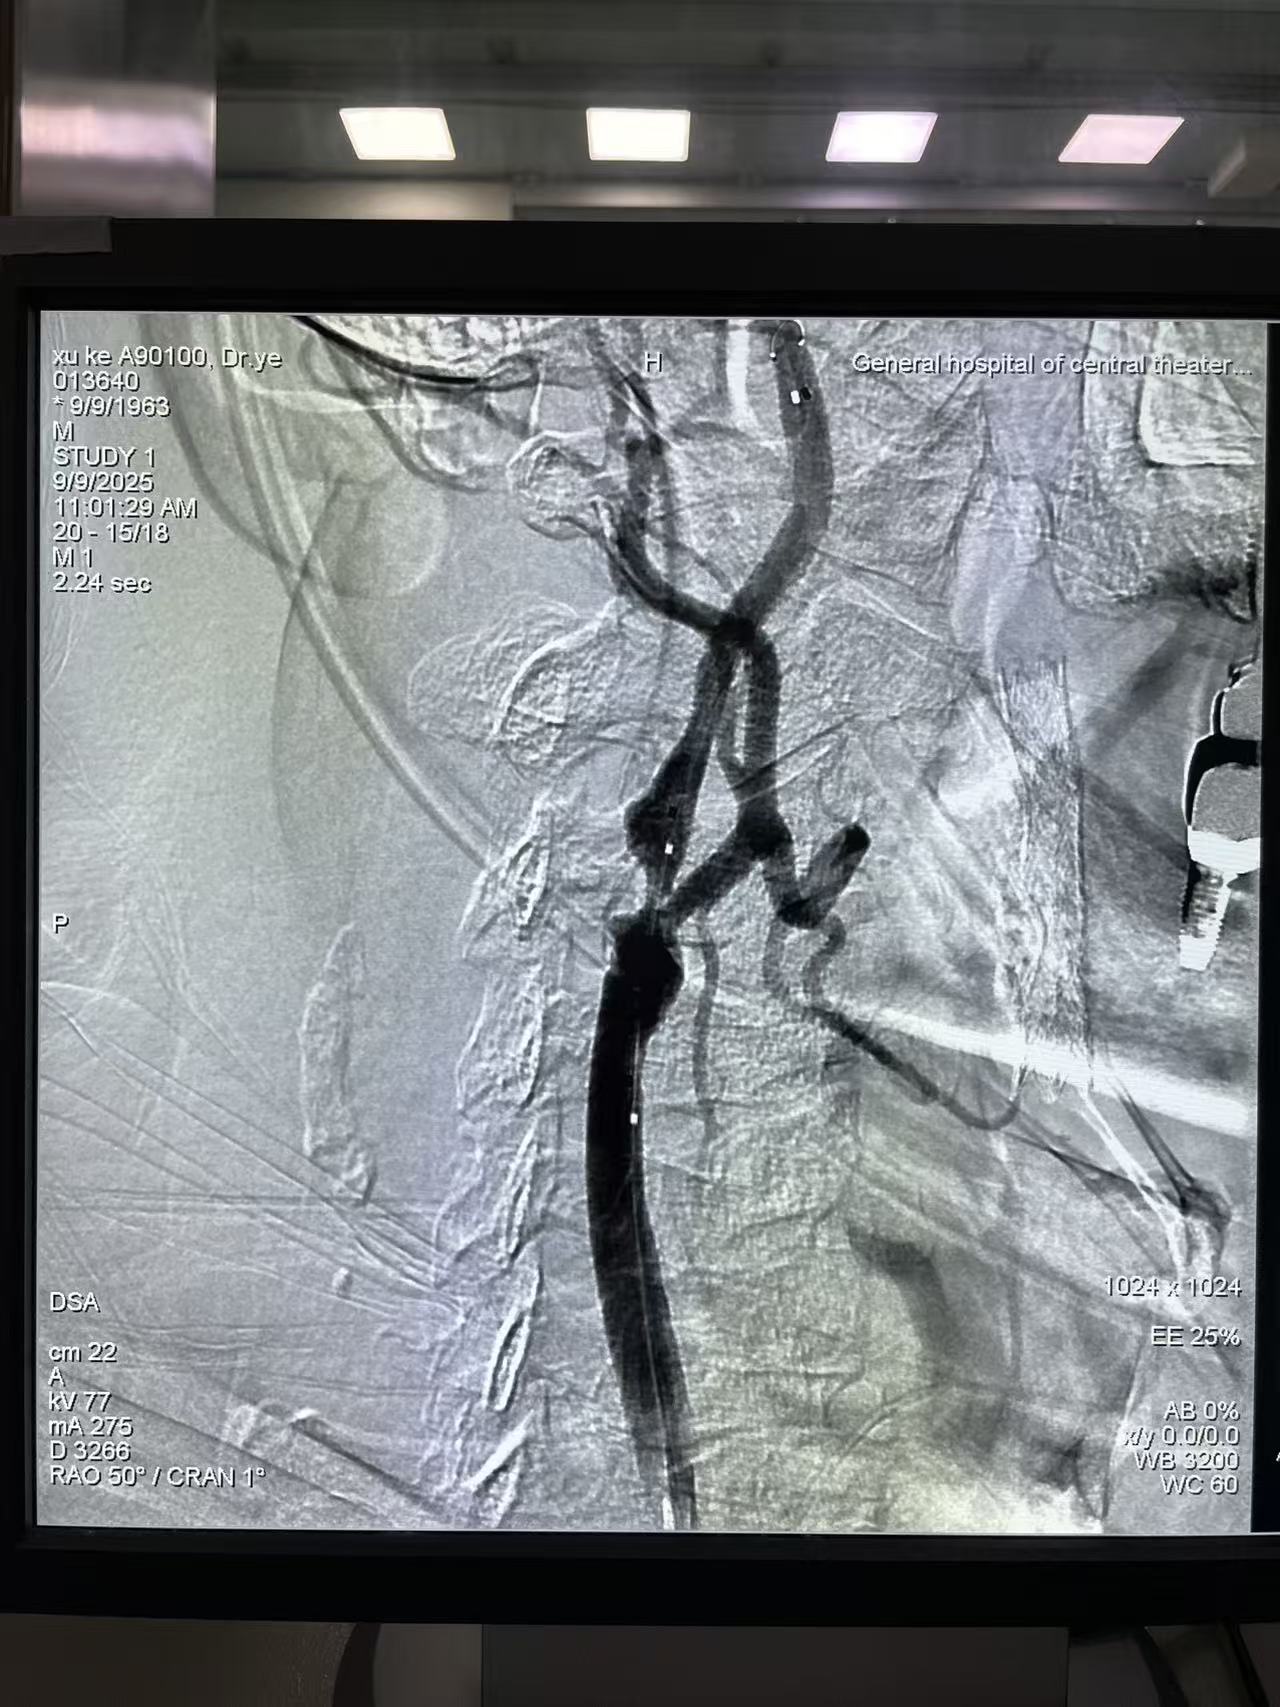

他的技术突破极具标志性——曾独立完成国际首例“冠脉+颅内血管并联狭窄(前循环大脑中动脉+后循环椎动脉)一站式介入手术”,带领团队完成百余例泛血管疾病综合介入治疗,充分展现了跨系统血管诊疗的整合能力。此外,他在选择性心脑血管造影、血管封堵术等基础介入技术上经验深厚,年均主刀手术超600例,累计收治患者超9万人次。

双侧颈动脉狭窄合并椎动脉狭窄患者,同期干预(一次完成三处病变)与分期干预(分次完成)的选择,需在疗效、安全性、经济性间综合权衡,具体决策需结合患者个体病情、血管解剖特点及医疗中心技术能力确定,以下为核心分析及文献支撑方向:

1. 优先评估患者耐受性:若患者年龄<70岁、无严重基础病(如心功能不全、慢性肾功能衰竭)、血管解剖条件允许(如血管直径>4mm、无严重钙化),可参考《Stroke》2023年发表的研究,尝试同期干预(但需严格控制手术时间<4小时);若患者年龄≥70岁、合并2种以上基础病,或血管钙化评分>8分(Agatston评分),建议分期干预,首次优先处理狭窄率>70%或供血区域关键的血管(如优势侧颈动脉)。